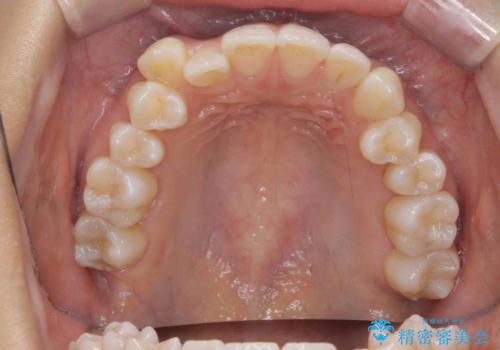

【審美装置】八重歯気になる

- 八重歯と叢生を主訴に来院されました。なるべく健康な歯を残したいという患者様の希望から、右側上下4番抜歯をしてワイヤー矯正する治療計画を立てました。

なるべく健康な歯を残したいという患者様の希望から、右側上下4番抜歯をして矯正しました。片側抜歯だったため、正中がズレないように気をつけながら治療を行いました。

正中もズレることなく主訴である八重歯と叢生を改善することができました。